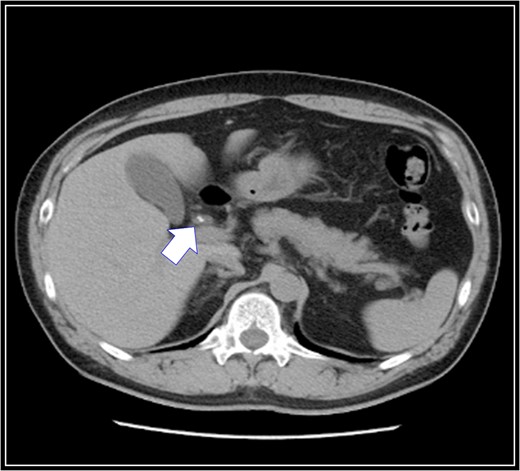

The patient was placed in supine position. Initially, intracorporeal procedures were performed in the laparoscopic view through four trocars (one 12-mm port and three 5-mm ports). We considered using intraoperative cholangiography to explore the right accessory hepatic duct. We incised the serosa by the neck of the gallbladder, used the Rouviere sulcus as a landmark, and peeled off the Calot triangle near the gallbladder. Subsequently, we identified the cystic artery and isolated it. Then we identified the cystic duct, and we inserted a cholangiography tube into it. The intraoperative cholangiography image showed that the right accessory hepatic duct branching from the cystic duct dominated an anterior segment of the right hepatic lobe (Fig. 3). Next, we isolated the cystic duct while preserving the right accessory hepatic duct. We resected the gallbladder. The total operating time was 125 min, and the intraoperative blood loss was minimal. Since the patient's postoperative course was uneventful, he was discharged 4 days later. We performed drip-infusion cholangiography-CT (DIC-CT) 48 days postoperatively. The DIC-CT scan demonstrated that the right accessory hepatic duct was intact, and it dominated an anterior segment of the right hepatic lobe (Fig. 4).

Drip-infusion cholangiography-computed tomography scan. Forty-eight days postoperatively, the right accessory hepatic duct is intact (black arrow), and it dominates an anterior segment of the right hepatic lobe, as indicated by the intraoperative cholangiography scan.